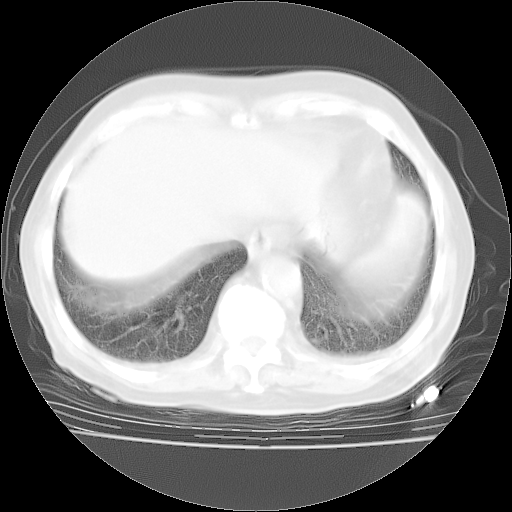

4月28日肺部CT——再次出现类似去年5月9日——透光度降低,“间质性”改变。

4月28日肺部CT——再次出现类似去年5月9日——磨玻璃样、间有“粟粒样”改变。

4月28日肺部CT

个人阅读4.14日肺部CT平扫:纵隔窗无异常,但肺窗示:双下肺内、后基底段有片絮状侵润影,部位以后基底段为著,以间质改变为主,呈急性肺泡炎征像,和首次住院影像学有相似之处。仅是个人读片,明日请相关专家再读片哈。其它建议同上。